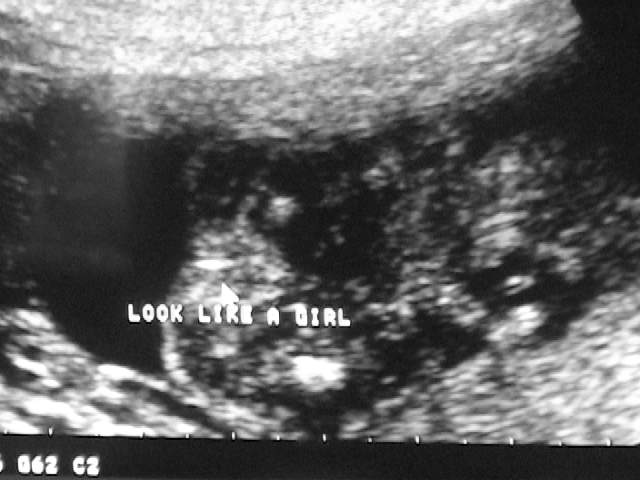

11. It’s a Girl!

• 2007-04-03

• Dave Allen Barker Jr

We got a sonogram today, and we have a girl on the way!

[Sonogram] Look Like A Girl